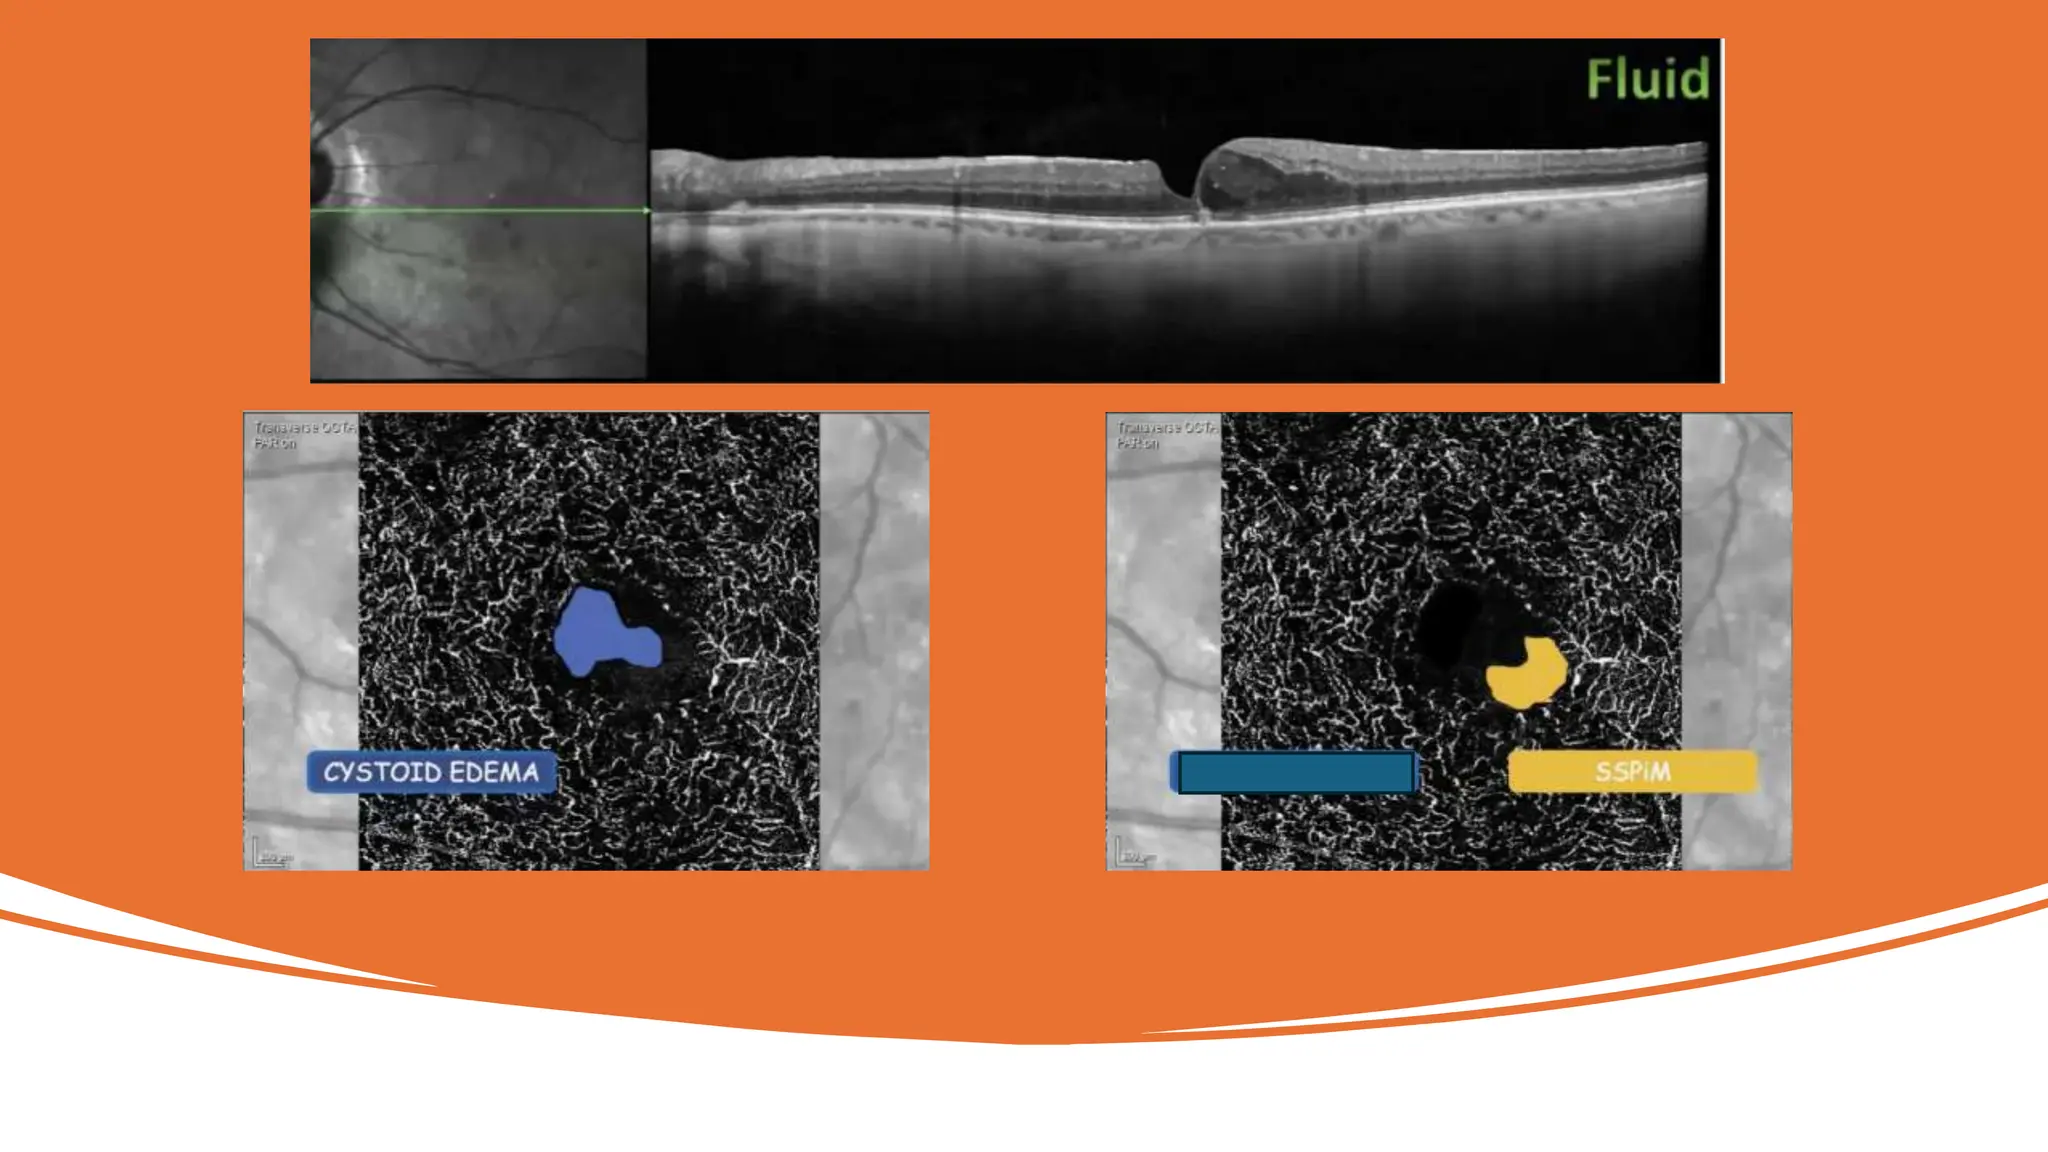

OCT /OCTA

Imaging

Fluid:

• Intra or subretinal

• Hyperreflective material

• Confluent cystic spaces

• Suspended Scattering Particles In

Motion

(SSPiM)